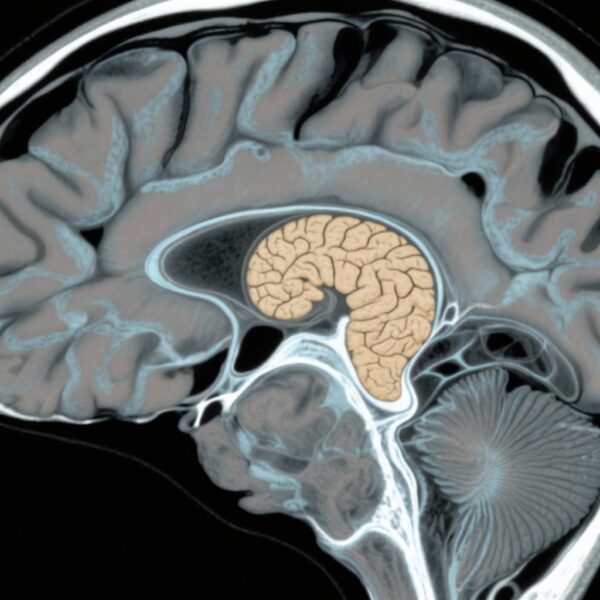

- 亜硝酸ガスへの曝露が増えると、海馬体積が小さくなる傾向があり、NO2とPM10への曝露が高齢者の脳室体積の増大と関連しています。

この人口ベースのコホート研究では、1946年3月の1週間に生まれたNSHD参加者を対象とした縦断データを利用しました。認知評価には43歳から69歳までの最大2,148人の参加者が含まれ、Insight 46神経画像サブスタディには69〜71歳の502人が含まれました。大気汚染への曝露指標(NO2、NOx、PM10、PM2.5、粗粒子状物質(PMcoarse)、PM2.5吸収度)は、中年期(45〜64歳)の間隔で割り当てられ、早期の汚染物質(黒煙、二酸化硫黄)を調整しました。認知アウトカムには、言語記憶(15項目リコール)、情報処理速度(視覚探索タスク)、全体的な認知状態(Addenbrooke’s Cognitive Examination III)が含まれました。脳MRIでは、総脳容積、脳室容積、海馬容積、白質高信号容積を測定しました。社会人口統計学的な混在因子(喫煙、地域の困窮度)は、一般化線形混合モデルを使用して制御されました。

神経画像サブスタディでは、453人の参加者が分析され、NOxへの曝露が高まると、海馬体積が小さくなることが示されました(β -0.088、95% CI -0.172 to -0.004)。これは、記憶とアルツハイマー病に関連する重要な領域です。さらに、NO2とPM10への曝露は、脳室体積の増大(NO2 β 2.259、95% CI 0.457 to 4.061;PM10 β 1.841、95% CI 0.013 to 3.669)に関連していました。これは、脳萎縮のマーカーです。白質高信号体積には一貫した関連はありませんでした。